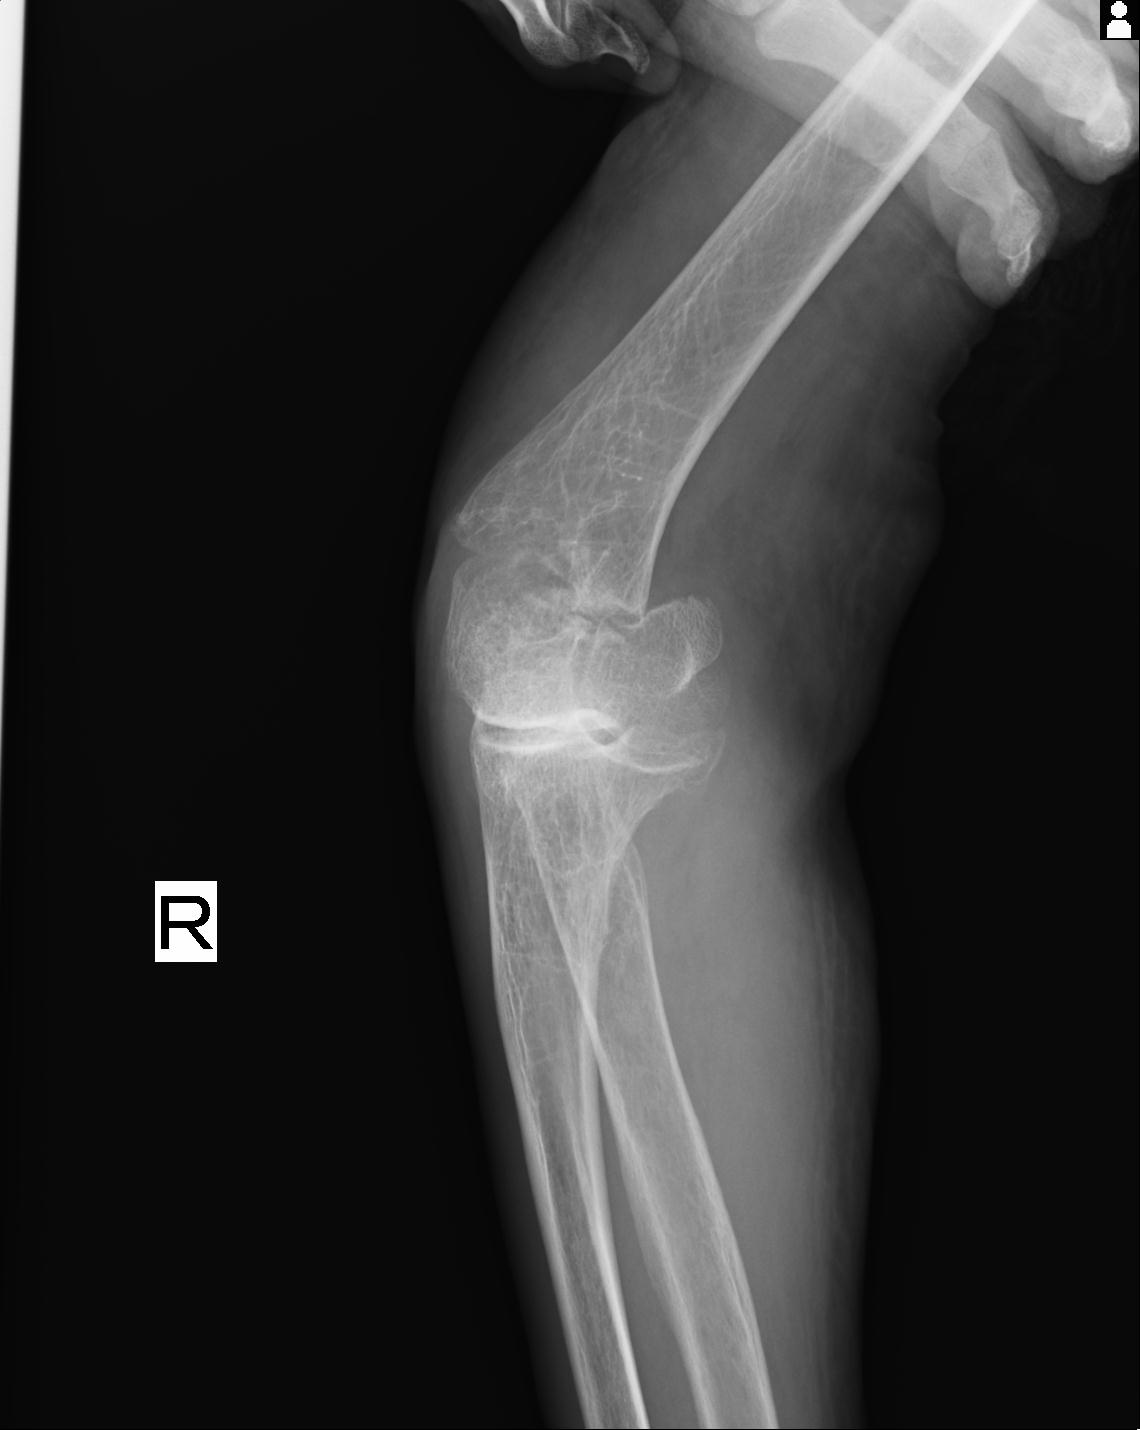

2271 1/25 右肘 4R 1/27 4R 3/24 4R 94歳女性 右通顆骨折